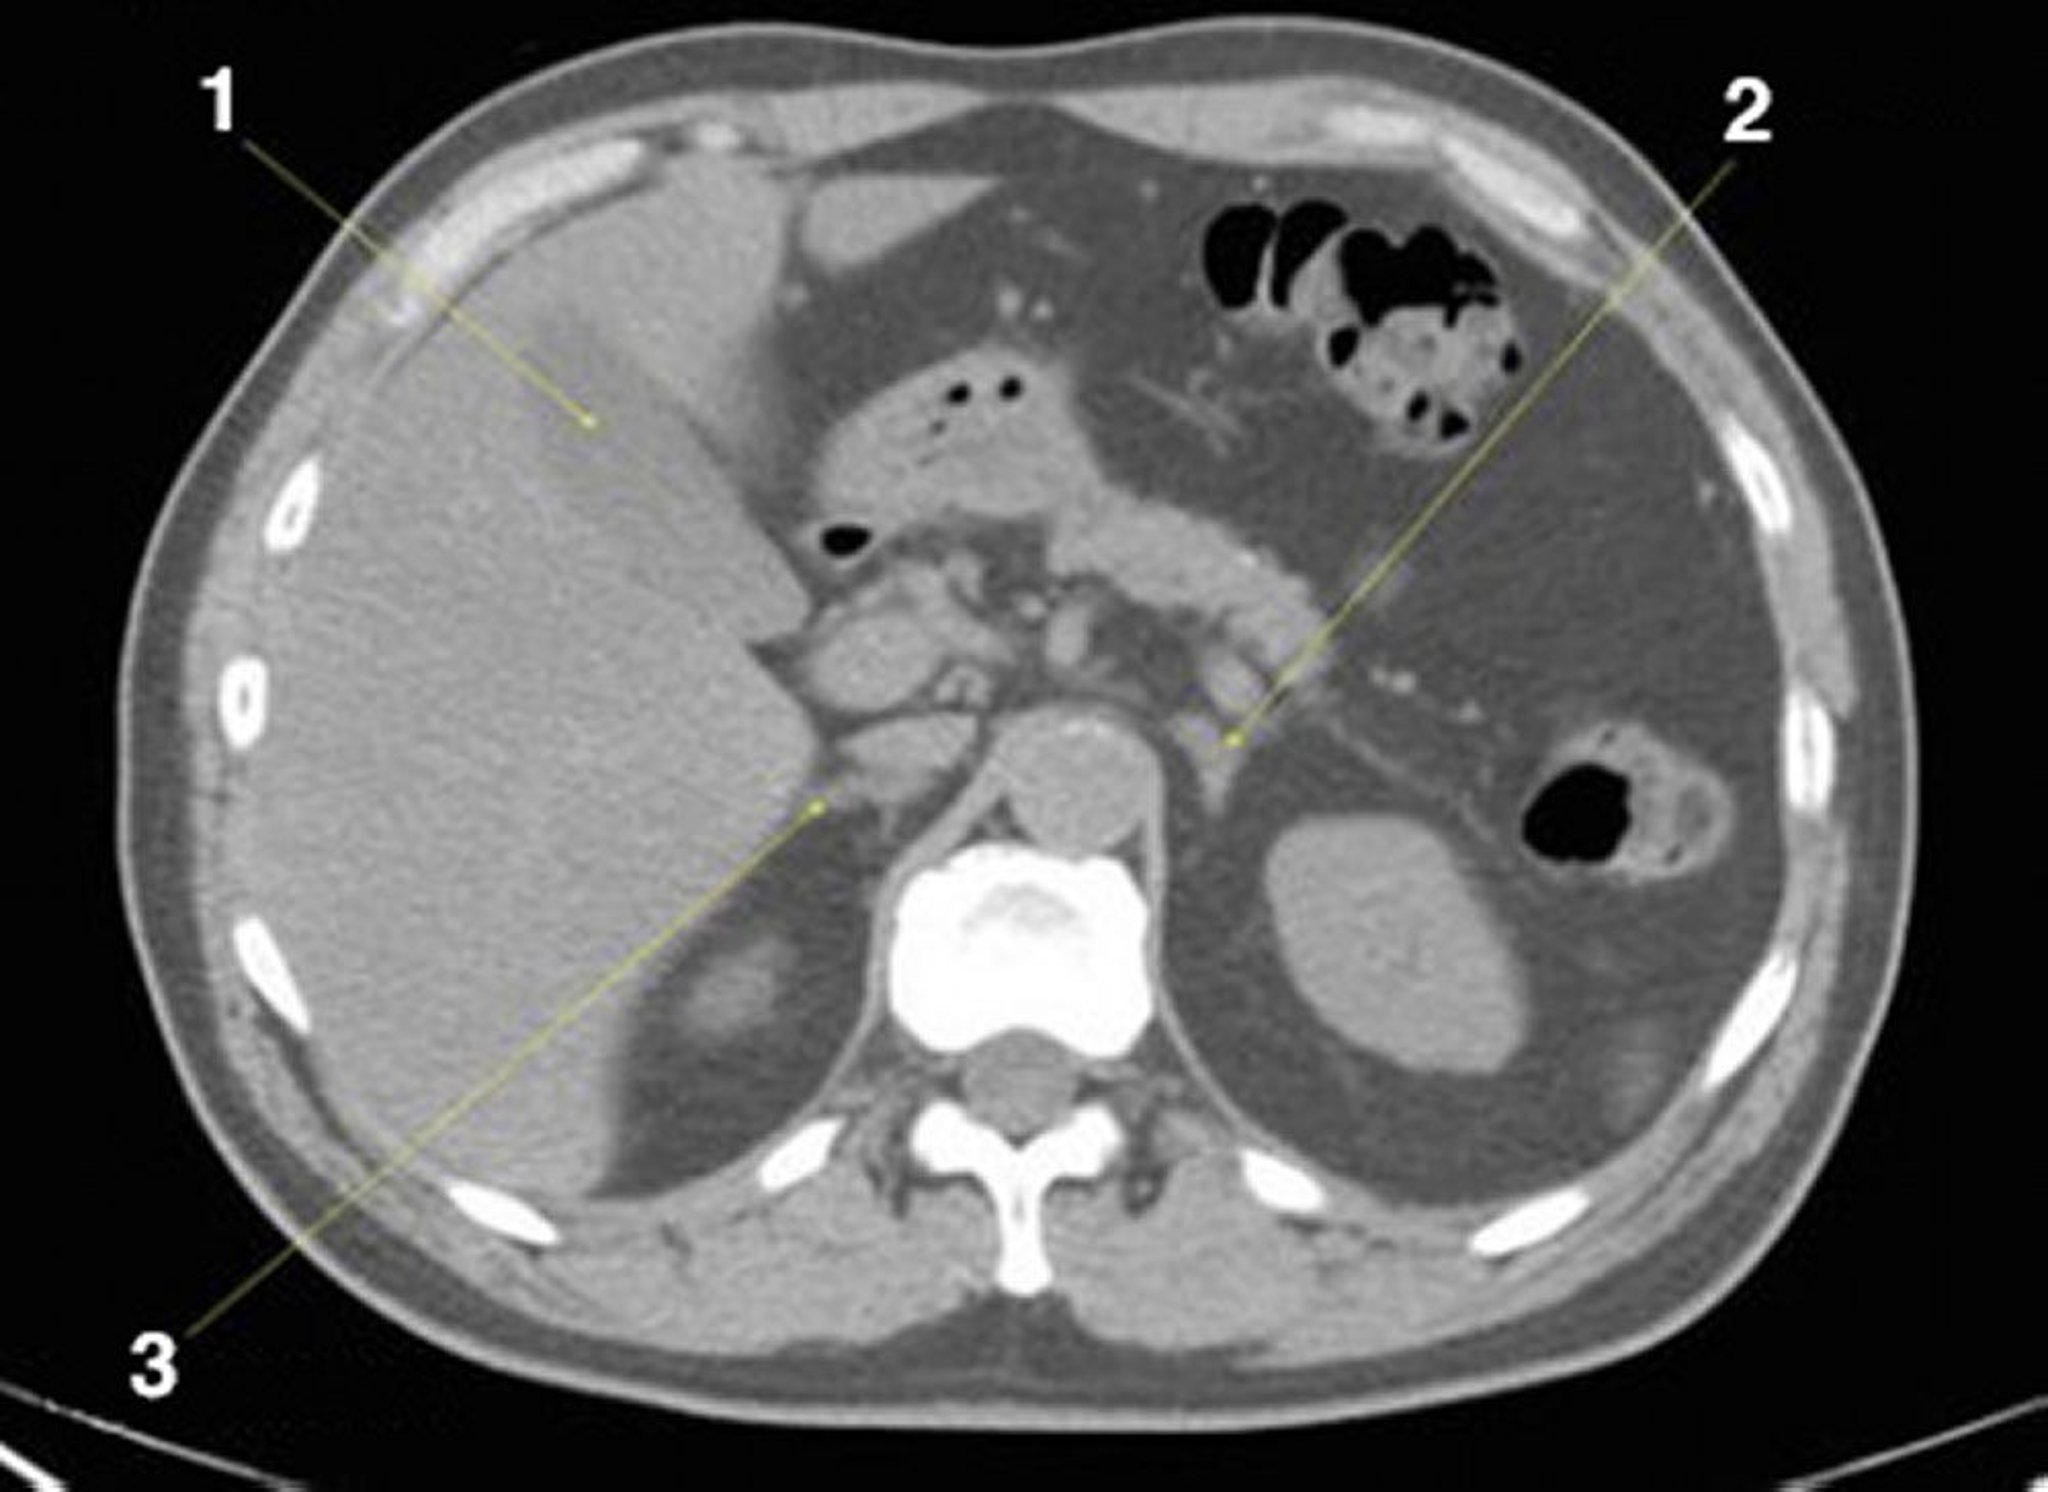

Tomografía computarizada sin contraste de abdomen y pelvis que muestra anatomía normal (corte 8)

1 = vesícula biliar; 2 = glándula suprarrenal izquierda; 3 = glándula suprarrenal derecha.